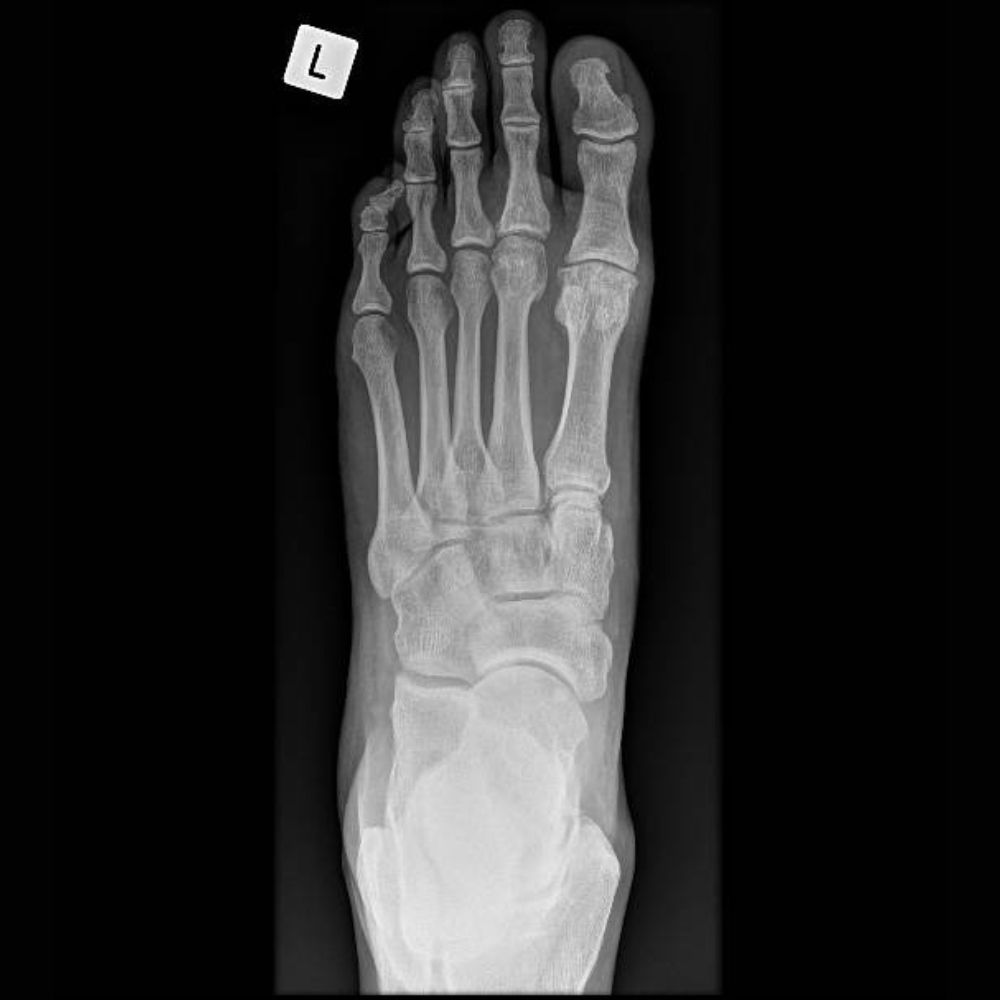

Adult with Fusion (Arthrodesis) of the Left Hallux Rigidus (Osteoarthritis of the Big Toe)